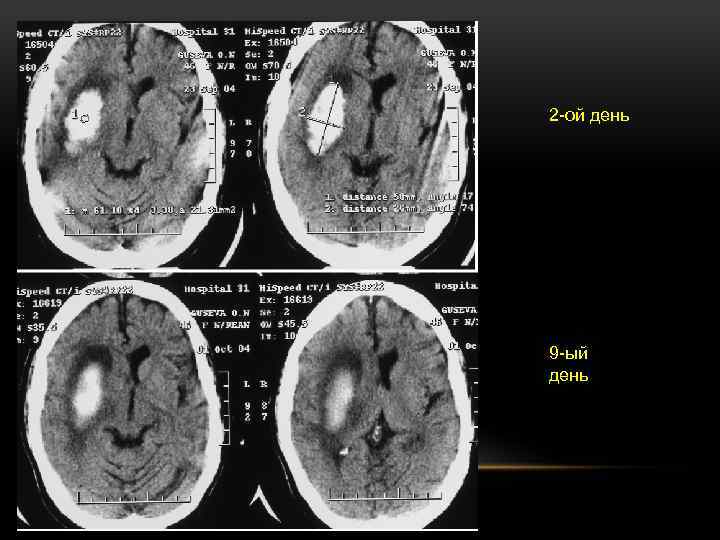

2 -ой день 9 -ый день

ДИАГНОСТИКА ВНУТРИМОЗГОВЫХ КРОВОИЗЛИЯНИЙ • «Золотым стандартом» для определения кровоизлияния в головной мозг остается рентгеновская КТ, проведение которой считается необходимым для исключения ВМК у пациентов с инсультом в остром периоде. На томограммах ВМК представляет собой очаг повышенной плотности вещества головного мозга, округлой или овальной формы, иногда наблюдаются признаки объемного воздействия на ликворосодержащие пространства и желудочковую систему разной степени выраженности в зависимости от размеров и локализации кровоизлияния (Кротенкова М. В. и др. , 2010). • Эволюция изображения ВМК по данным рентгеновской КТ подчиняется определенной закономерности

Эволюция изображений ВМК. КТ: а — первые сутки; б — третьи сутки; в — седьмые сутки; г — 14 -е сутки; а б в д — 21 -е сутки. Феномен «тающего кусочка сахара» , постепенное снижение плотности очага кровоизлияния г д